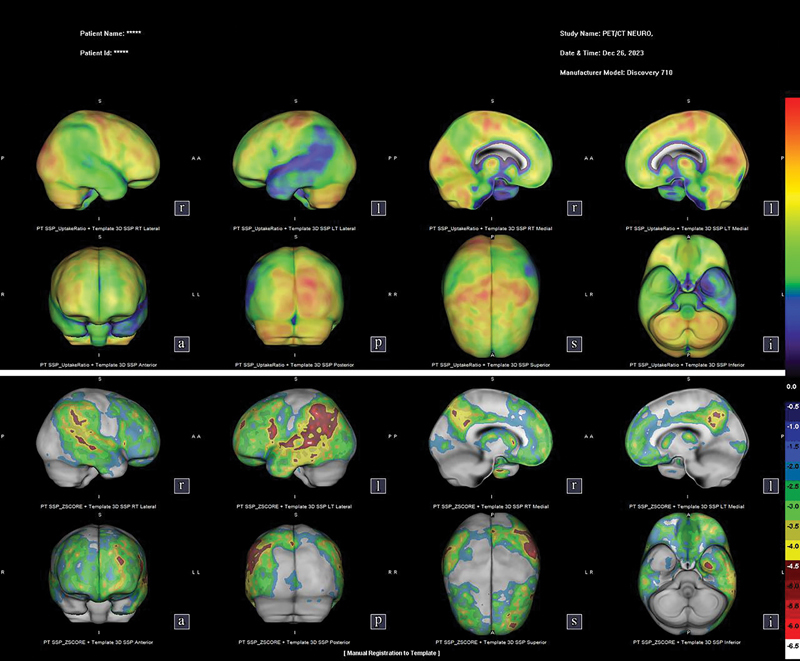

Abstract Image